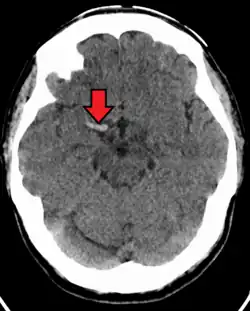

Cerebral venous sinus thrombosis

Cerebral venous sinus thrombosis (CVST) is a rare form of stroke which results from the blockage of the dural venous sinuses by a thrombus. Symptoms may include headache, abnormal vision, any of the symptoms of stroke such as weakness of the face and limbs on one side of the body and seizures. The diagnosis is usually made with a CT or MRI scan. The majority of persons affected make a full recovery. The mortality rate is 4.3%.[15]